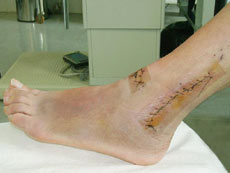

Für die nächsten sechs Wochen sind Rollstuhl und Krücken angesagt...